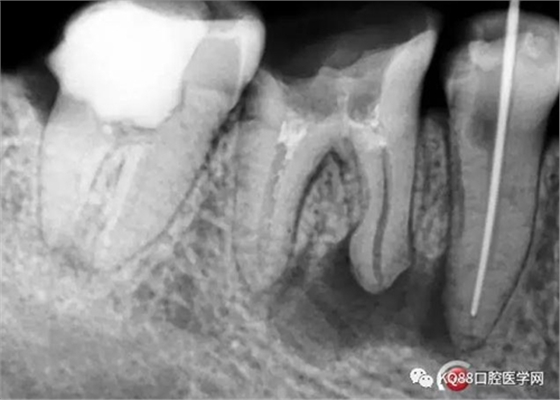

處理與結(jié)果:45局麻去髓,在確定工作長度時(shí)拍X線片顯示:46近中根尖周稀疏影,且邊緣呈淡薄云霧狀。

例2 45根管測量時(shí)X線片所見